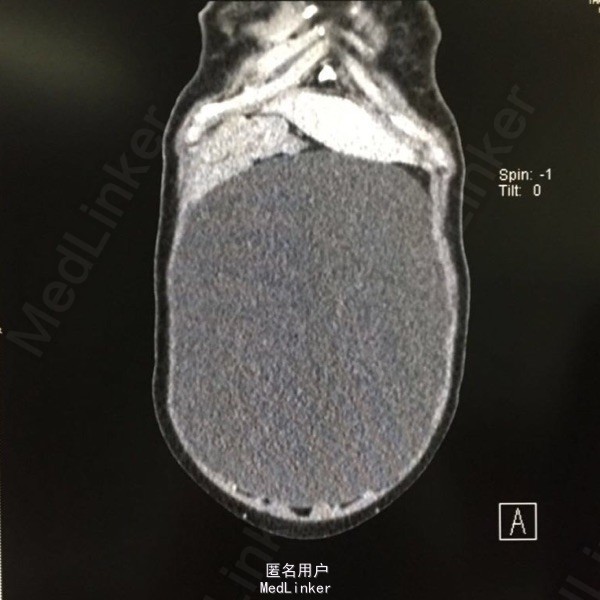

患者女性,54岁,因发现盆腔巨大包块半月余入院。半月前患者外院体检行B超提示腹部积水,遂至我院就诊。患者已绝经5年,有高血压病史5年,自诉血压控制可。

查体:腹部膨隆,可扪及一巨大包块,上至剑突,下达盆腔,双附件区触诊不满意。 辅查:我院腹部CT:盆腹腔可见一巨大囊性水样密度包块,大小约27.1×12.8cm,内未见分隔及壁结节影,考虑为右侧附件来源,囊腺瘤可能;子宫前壁肌瘤可能。

入院诊断:盆腔包块、子宫肌瘤。入院后完善相关检查后,行双附件切除术+子宫肌瘤剔除术,术中见约30×30×25cm大小的囊性包块,来源于右侧卵巢,在囊肿表面做一小切口,吸出淡黄色囊液约3000ml。术后病理示:卵巢浆液性囊腺瘤。